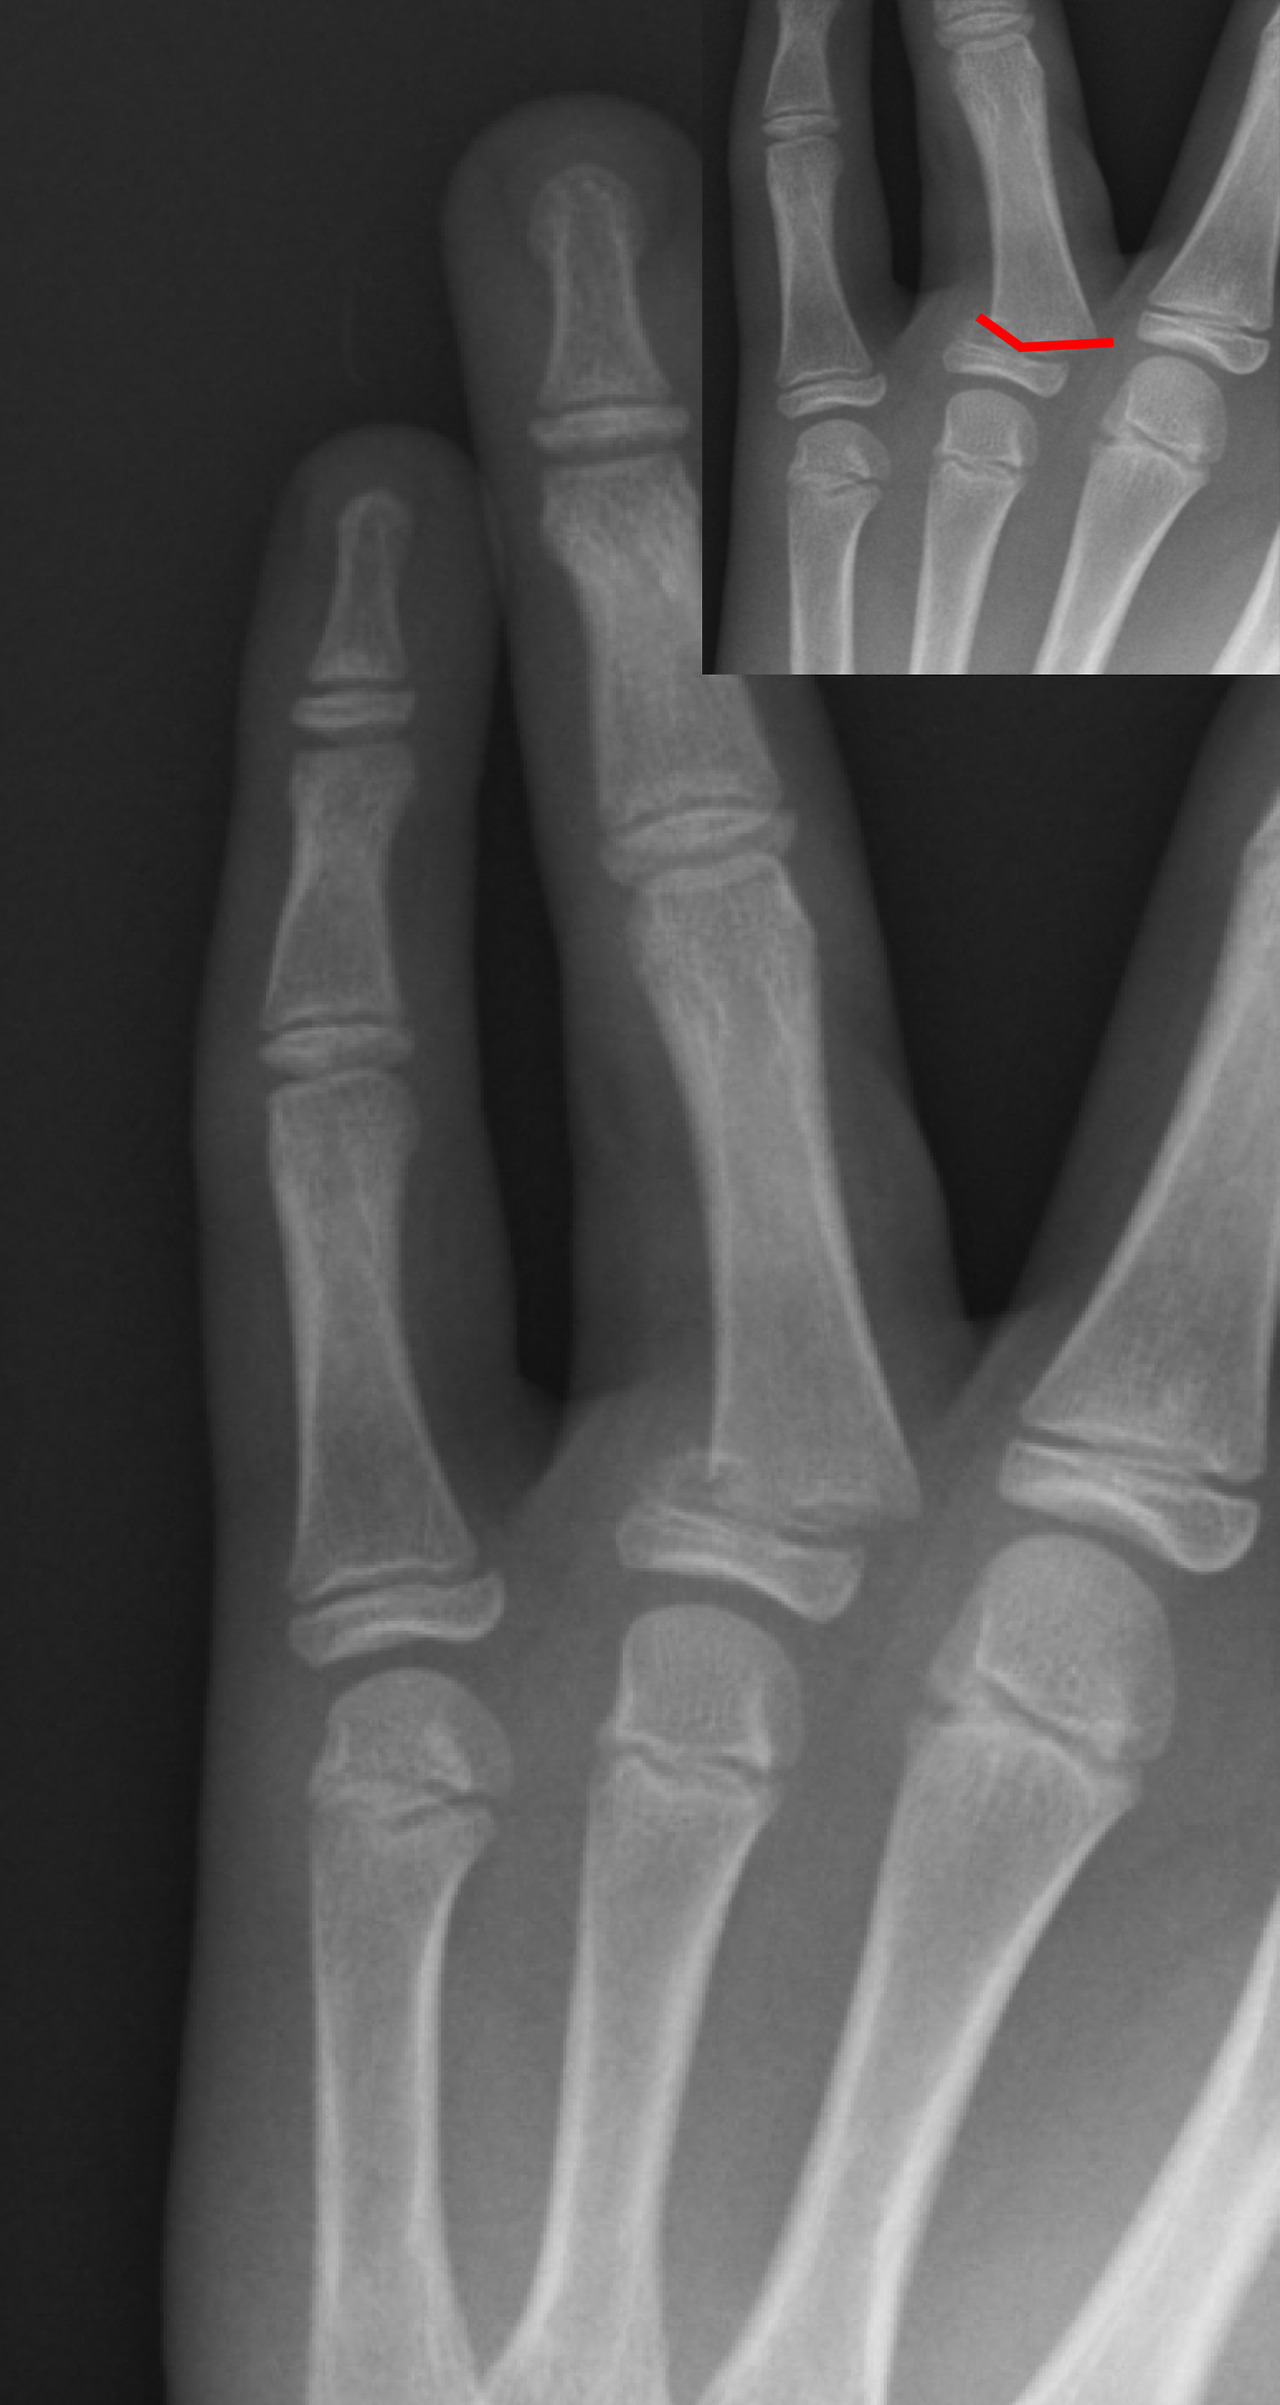

진료비와 검사비

- X-ray 촬영: 기본적으로 뼈 상태를 확인하기 위해 X-ray 촬영이 이루어지며, 병원에 따라 2~5만 원 내외의 비용이 들 수 있습니다.